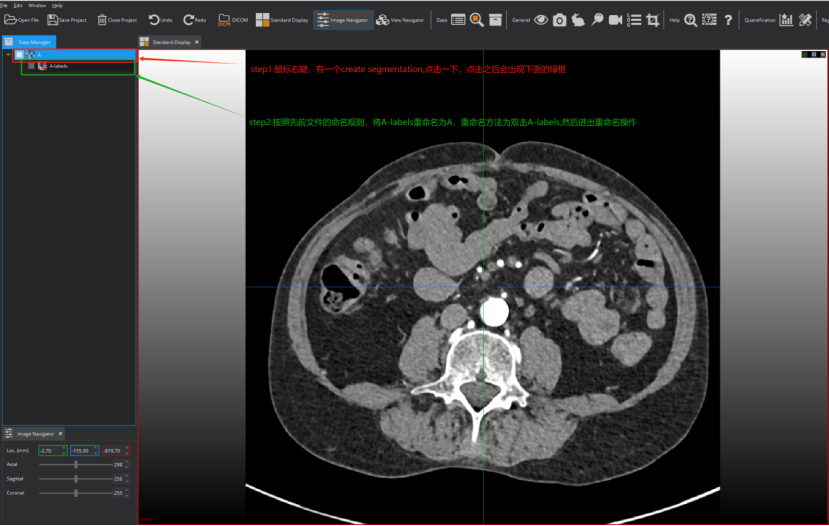

Step 5: 创建分割。这里需要注意,对create segmentation之后的文件进行重命名操作,具体实现看图片文字说明: